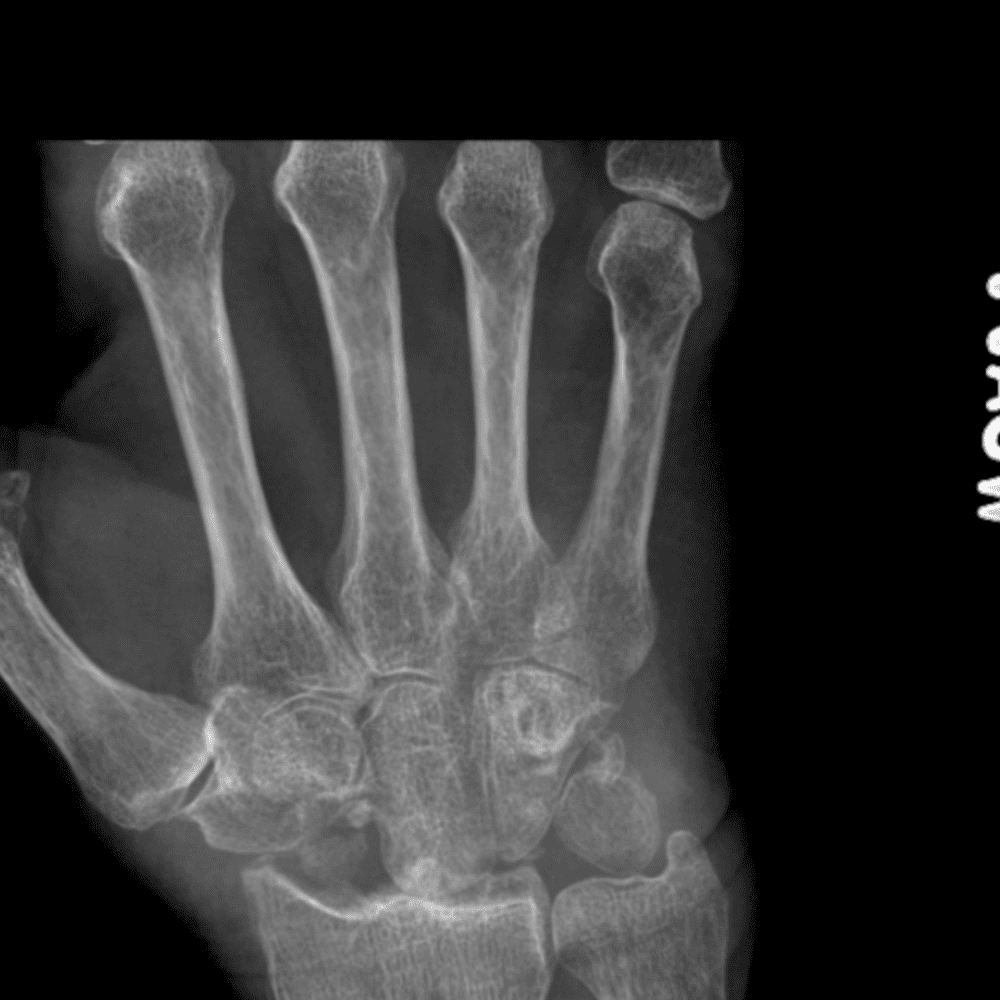

Simuliert den Dienst durch subtile oder schwierige Fälle und einige Normalbefunde.

30 Fälle